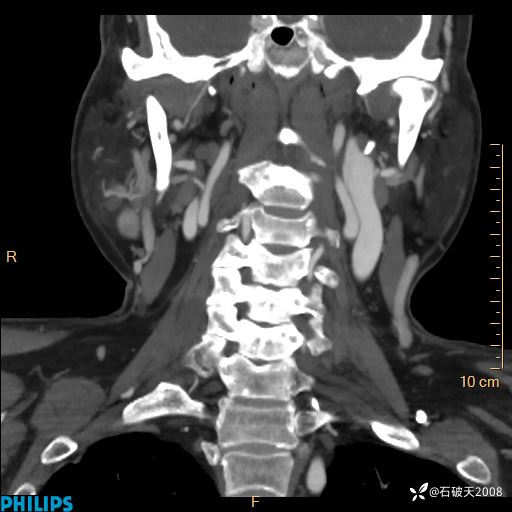

静脉期